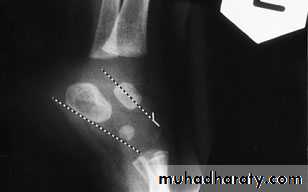

X-ray:

Lines can be drawnthrough the long axis of the talus parallel to its medial border & aline passing in the longtudinal axis of calcanium parallel to its latral border should de 20-40 digree